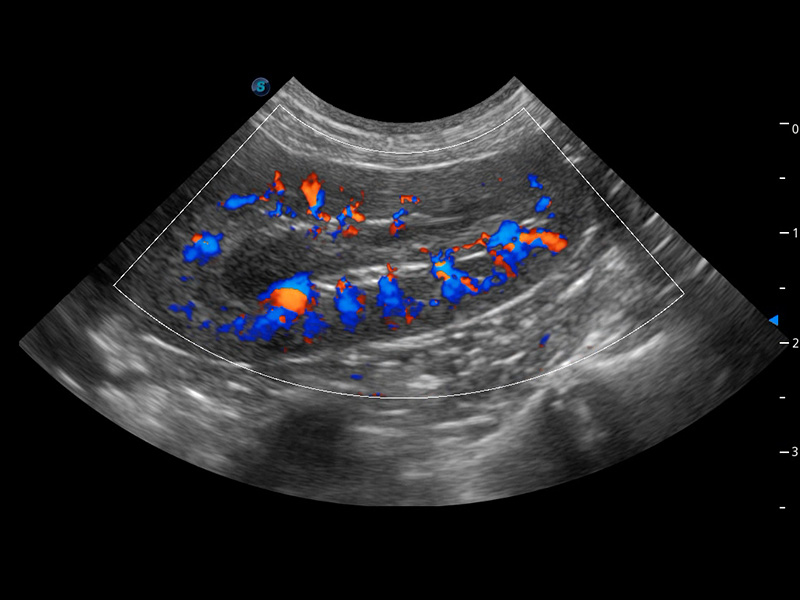

ProPet 60 作为一款高端台式动物超声设备,为动物医生的日常诊断提供了一系列贴合动物临床需求、解决临床实际问题的高级成像功能。凭借全系列高清探头,满足医生对腹部、心脏、生殖、浅表、肌骨等成像的所有需求,切实帮助您提升检查效率,提高诊断信心。

动物是人类最亲密的朋友和最值得信赖的伙伴。米兰官方网站也一直致力于探索动物专用的超声影像解决方案。 全新推出的ProPet系列,是米兰官方网站在动物超声影像智能化、专业化、精准化的一次跨越式革新。动物不能用言语来表述自己的不适,通过超声影像,ProPet系列搭建了动物医生与不同物种沟通的“桥梁”,为动物医生注入了“治愈之力”。